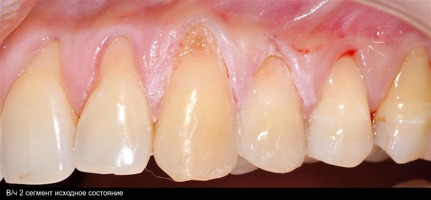

В области от 1.6 до 2.6 и от 3.6 до 4.6 все зубы имеют некариозные поражения разной степени, такие как эрозии эмали и клиновидные дефекты, вовлекающие в процесс ткани эмали и дентина. Подвижности зубов не выявлено (рис. 1а-е) [9].

При анализе и описании компьютерной конусно-лучевой томографии (рис. 2а-г) была выявлена генерализованная первичная дегисценция вестибулярной пластинки кости от 1/2 до 3/4 длины корней зубов, зубной ряд целостный, все зубы витальны, кариозных поражений нет. Тип кости 1-2 (Lechkolm и Zarb, 1983), первичная дегисценция вестибулярной костной пластинки превышает пределы возрастной атрофии.

Второй сегмент был прооперирован через 4 месяца после операций на нижней челюсти, область операции включила в себя зубы от 2.1 до 2.6.